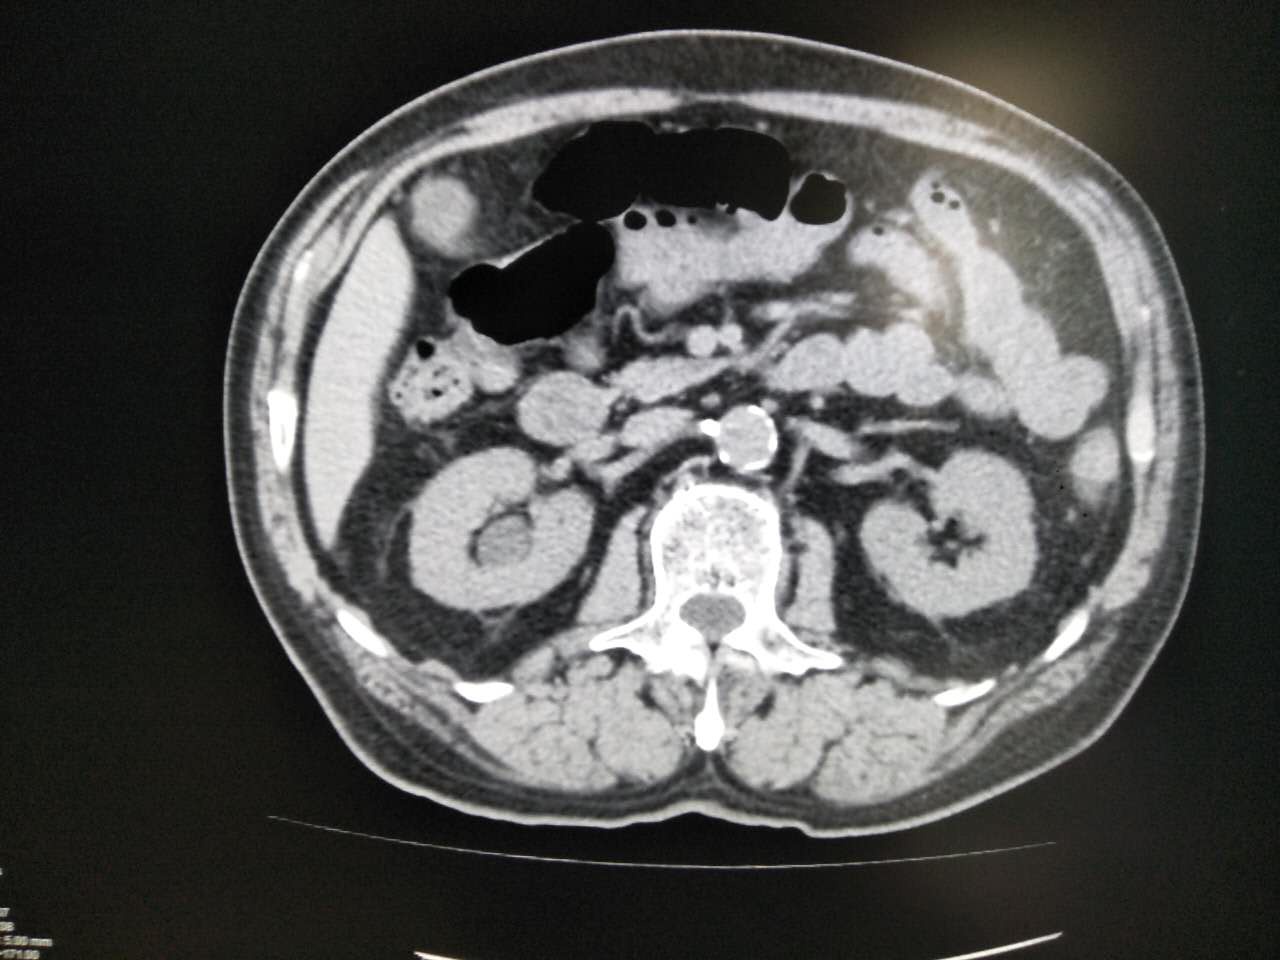

以下几例是胃肠道对比度较好的例子,可以清晰显示胃肠壁有无病变。